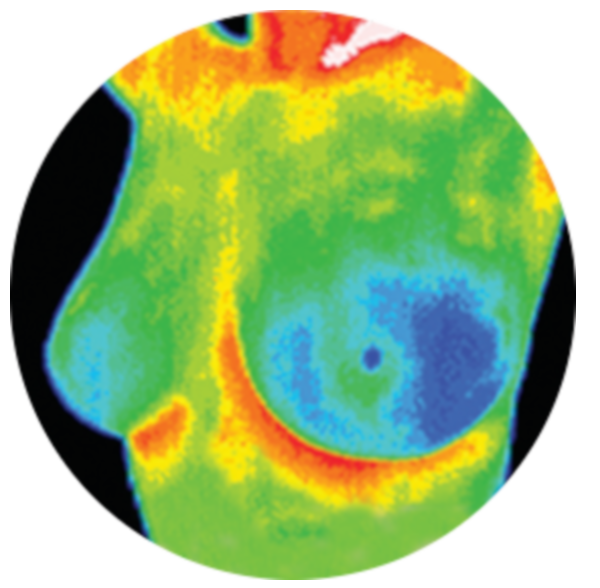

The Breast Screening Program offers free or low-cost breast screenings to women and men nationwide. UBCF covers various screening technologies such as mammography, ultrasound and thermography.

RodicaI wanted to take a moment to express my gratitude to the UBC Foundation for the grant I received. This money helped me to be able to take the steps necessary to monitor my health in the most accurate way possible… through Thermography. For the last several years I have been sent for countless mammograms and ultrasounds in order to monitor “questionable” spots on my breasts. During this time, I have felt unsure and uneasy knowing that many have gone through the same process only to find out they have advanced breast cancer. Upon researching Thermography at a friend’s recommendation, I was convinced that this process would provide assurance that I hadn’t had before. The process behind thermography aligned with everything I had researched about the body and the way cancer is fed. Thank you for enabling me to take the first step towards a sound accurate assessment of my health.

PeggyI want to thank all of you at UBCF for the great service you are offering to so many with your generous grants. My thermographer recommended UBCF to me for their grant program several years ago. My mother previously had breast cancer, so I want to keep a close eye on things. I have chosen to have thermograms rather than mammograms due to radiation concerns, and also due to the fact that thermograms detect tumors much earlier than mammograms, when disease is more treatable. Also, thermograms are much less invasive than mammograms. My health insurance doesn’t pay for thermography, though it will pay for mammography. Thanks to UBCF, I now have a choice again! Without the generous grant from UBCF, thermography wouldn’t have been an affordable option for me. Thank you so much from the bottom of my heart, for all you have done for me, and all you do for so many others, through all your grants and programs. You offer much needed, and appreciated, assistance to those in need. I am most grateful.